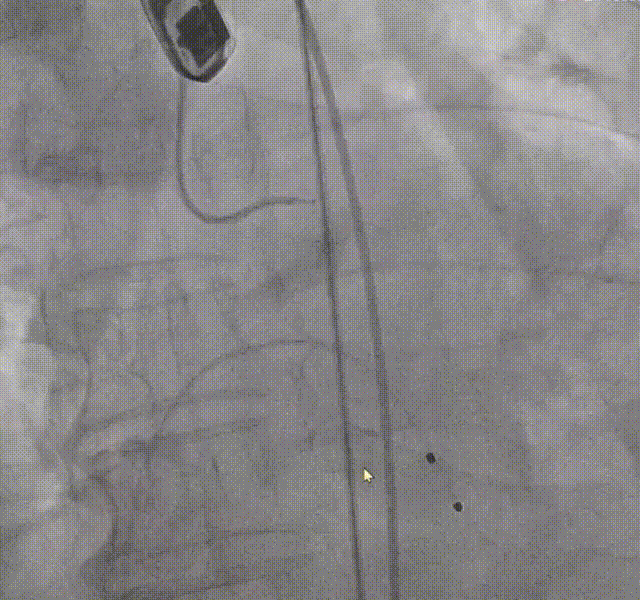

导丝跨瓣

主动脉根部造影